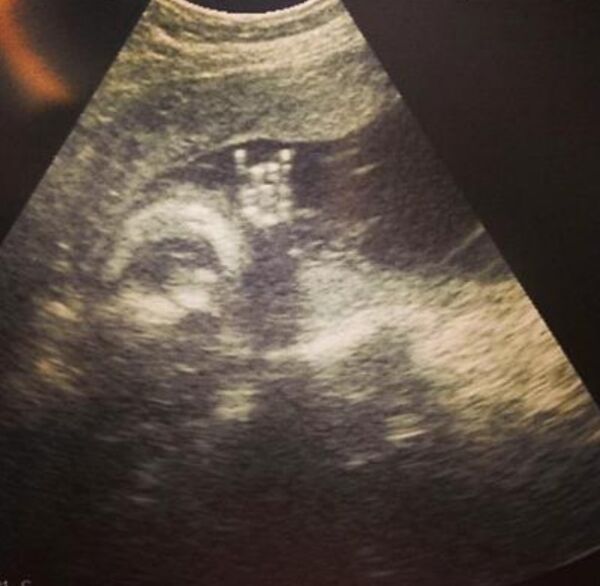

Bebekler anne karnında ne yapar?